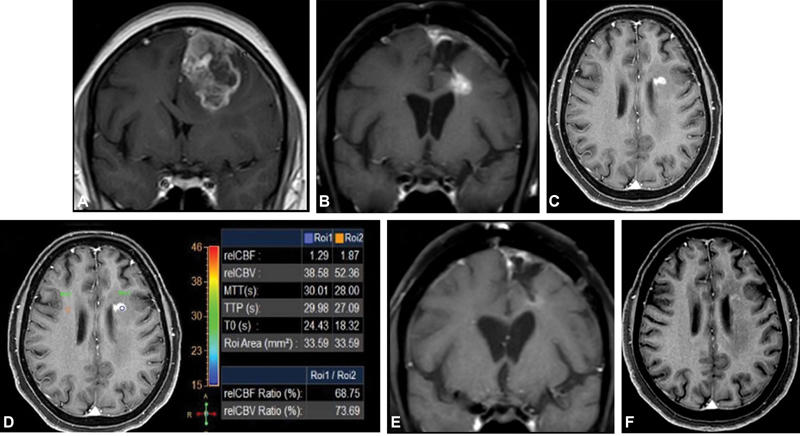

| Figure.3:(A) Left frontal lobe GBM at baseline MRI. (B and C) New enhancing nodule on post-surgery EBRT and adjuvant TMZ in left periventricular white matter showing hypoperfusion (D). Decrease in enhancement on follow-up (E and F). EBRT, external beam radiation therapy; GBM, glioblastoma multiforme; TMZ,

temozolomide.

| Figure.3:(A) Left frontal lobe GBM at baseline MRI. (B and C) New enhancing nodule on post-surgery EBRT and adjuvant TMZ in left periventricular white matter showing hypoperfusion (D). Decrease in enhancement on follow-up (E and F). EBRT, external beam radiation therapy; GBM, glioblastoma multiforme; TMZ, temozolomide.